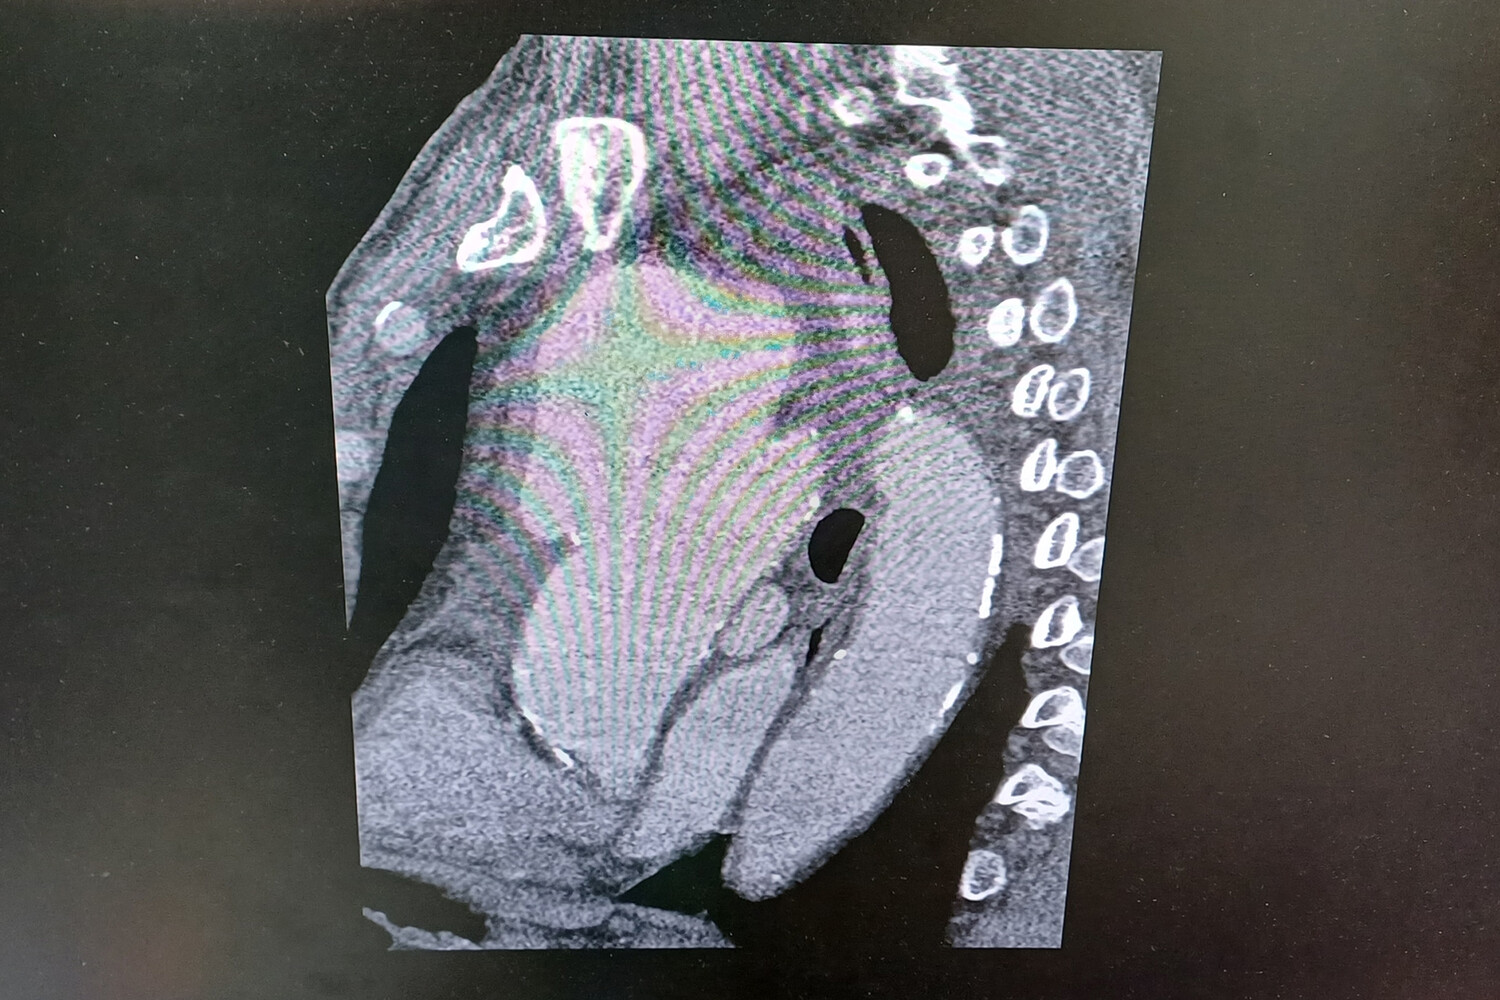

«Компьютерная томограмма подтвердила выпячивание аорты размером 9 на 9 сантиметров. Гигантская мешотчатая аневризма, больше, чем гусиное яйцо», — рассказал заведующий отделением №5 Рязанского кардиодиспансера Сергей Загородний.

По словам специалиста, аневризма сдавливала все близлежащие органы и ткани: трахеи, бронхи, верхнюю полую вену.